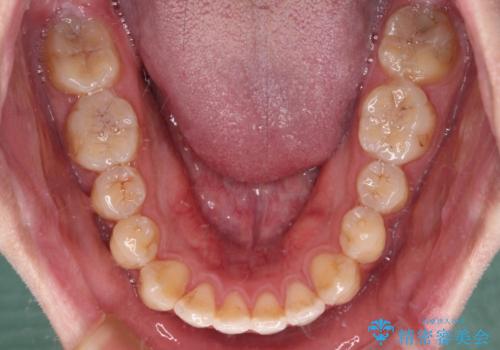

- クリアブラケット

- 1年4ヶ月

上顎側切歯(前から2番目の歯)が内側に転位している歯列は、インビザラインでは排列が困難であることが多いため、期間を短く、より良い仕上がりとするため、ワイヤー装置にて矯正治療を行うこととしました。

治療開始の頃は、食事や歯磨きが慣れず、装置が頻繁に脱落しましたが、2,3ヶ月ほどで慣れ、その後は1年ほどで治療を終えることができました。